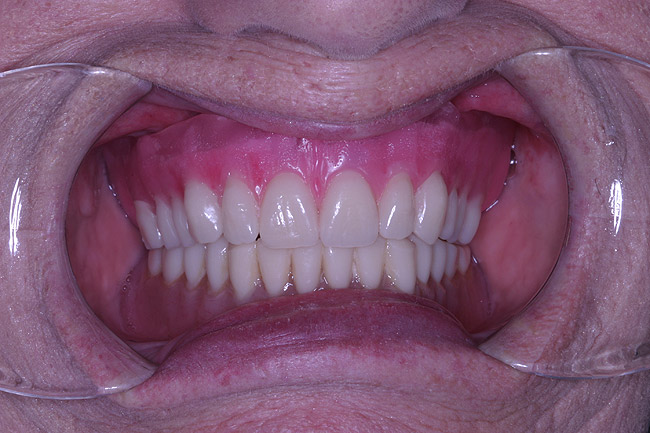

A 74-year-old woman presented with a chief complaint of a worn, stained,ill-fitting maxillary complete denture that she felt had minimal esthetic value (Figure 1). The optimal treatment plan consisted of a new, complete set of removable dentures but was not accepted by the patient due to financial constraints. The patient opted for a new maxillary denture with plans to replace the mandibular prosthesis at a later time.

The laboratory then fabricated a light-cured, stabilized base plate on which anterior and posterior teeth were set using the silicone putty mold made previously and waxed up to final contour and delivered to the office. The upper denture was tried in and a visual examination was performed to certify function, esthetics, phonetics, and patient/clinician satisfaction (Figure 14). The denture was sent back to the laboratory for final processing with the Ivocap Denture System (Ivoclar Vivadent North America, Amherst, NY). The prosthesis was trimmed and polished to high luster to prepare for final insertion (Figure 15). Additionally, Massachusetts requires denture labeling with a patient identifier (wearer's name, driver's license number, or Social Security Number, etc) for forensic purposes, and this was exacted according to state law.28

Figure 14  Retracted view of try-in.

Figure 14

Figure 15  Final case, postoperative.

Figure 15